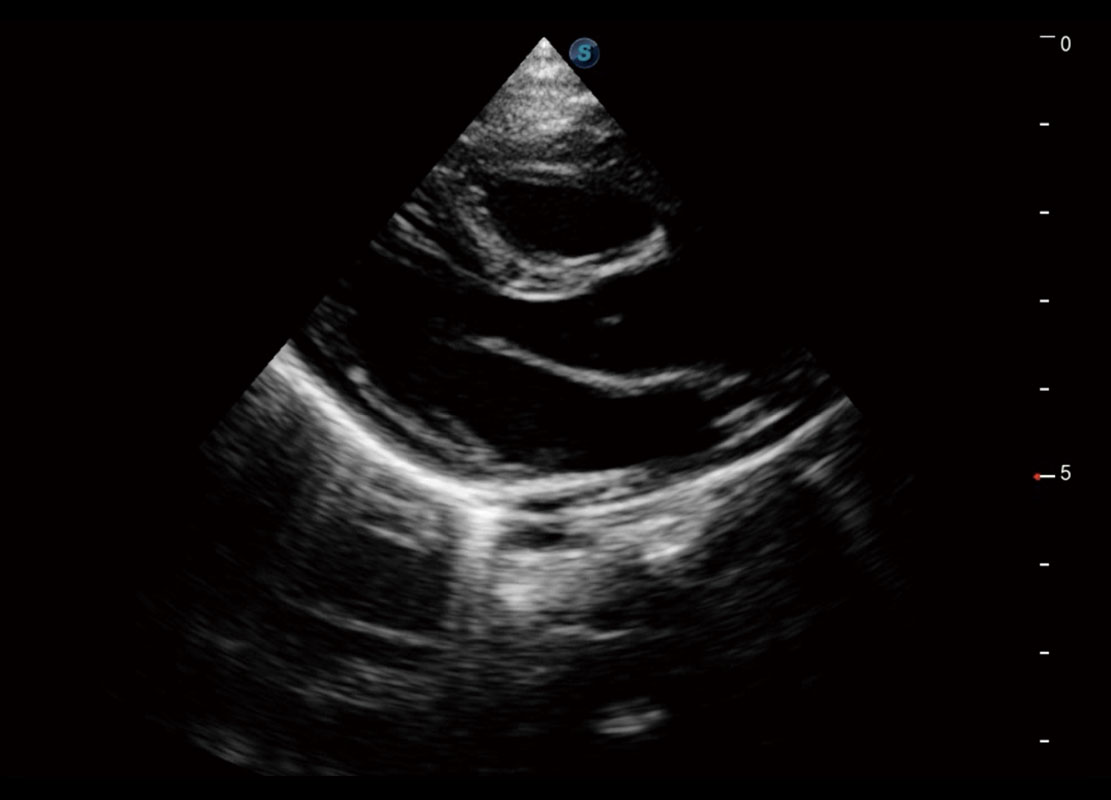

中晚孕筛查

P60提供简单易学易用的高端诊断工具,为您中晚孕筛查提供快速清晰的解剖信息。